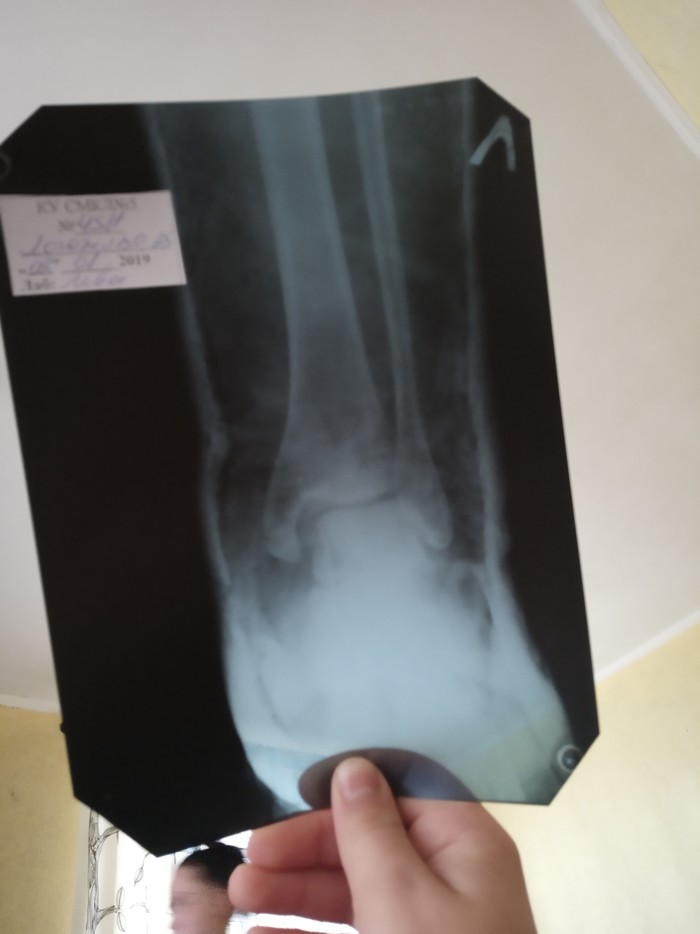

1 Basskillerz Помогите расшифровать (укр. язык) почерк 6 лет назад Друзья, недавно поламал ногу. Помогите расшифровать. На украинском языке. Показать полностью 2 [моё] Перелом Врачебный почерк Без рейтинга